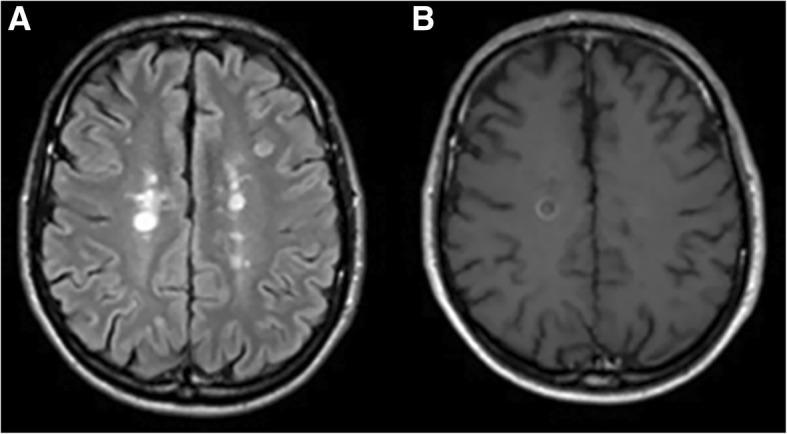

Cerebrospinal fluid (CSF) and serum samples from 60 MS patients were analyzed: 30 with magnetic resonance imaging (MRI) evidence of disease activity, gadolinium (Gd)-based contrast agent positive (Gd+), and 30 without MRI evidence of disease activity (Gd-). ATG5, Parkin, and lactate were measured using commercially available products.

Serum levels of ATG5, Parkin, and lactate were more elevated in Gd+ than in Gd- MS patients (p < 0.0001), and CSF concentrations of ATG5 and Parkin were greater in Gd+ than in Gd- MS (p < 0.0001). Our results demonstrated that molecular markers of autophagy and mitophagy are increased in CSF of MS patients during the active phases of the disease and that these catabolic markers, together with lactate, are also remarkably augmented in blood suggesting a role of these processes in MS pathogenesis and the possible use of these molecules as biomarkers of disease activity.